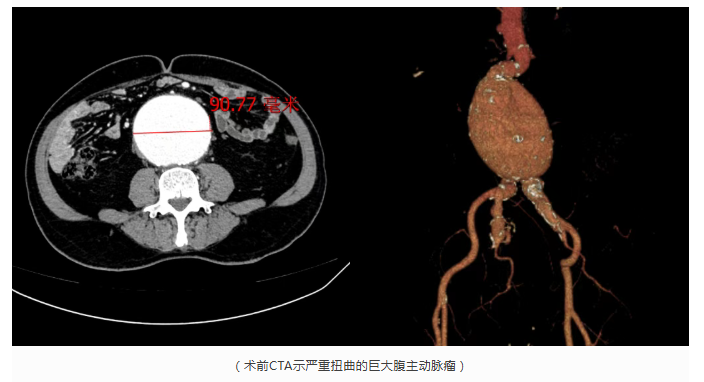

近日,秦先生(化姓)在家中突感腹部剧痛难忍大汗淋漓,紧急被家人送往附属仁济医院。血管外科主任医师薛冠华带领团队迅速响应,经过详细的上下腹CTA检查,结果让所有人大吃一惊:秦先生的腹主动脉发现一个巨大的瘤样扩张,最大直径达到9厘米,且形态不规则,破裂风险极高。

面对如此危重复杂的病例,薛冠华立即启动血管外科应急救治流程。然而,秦先生的病情远比想象中复杂:巨大的瘤体不仅瘤颈严重扭曲成“S”型,而且右侧髂总、髂内动脉也同样瘤样扩张,为手术带来了巨大挑战:如何在扭曲的血管通路中,将支架精准地送入目标位置并实现完美贴合,同时保护好盆腔脏器的血供,成为手术成败的关键。